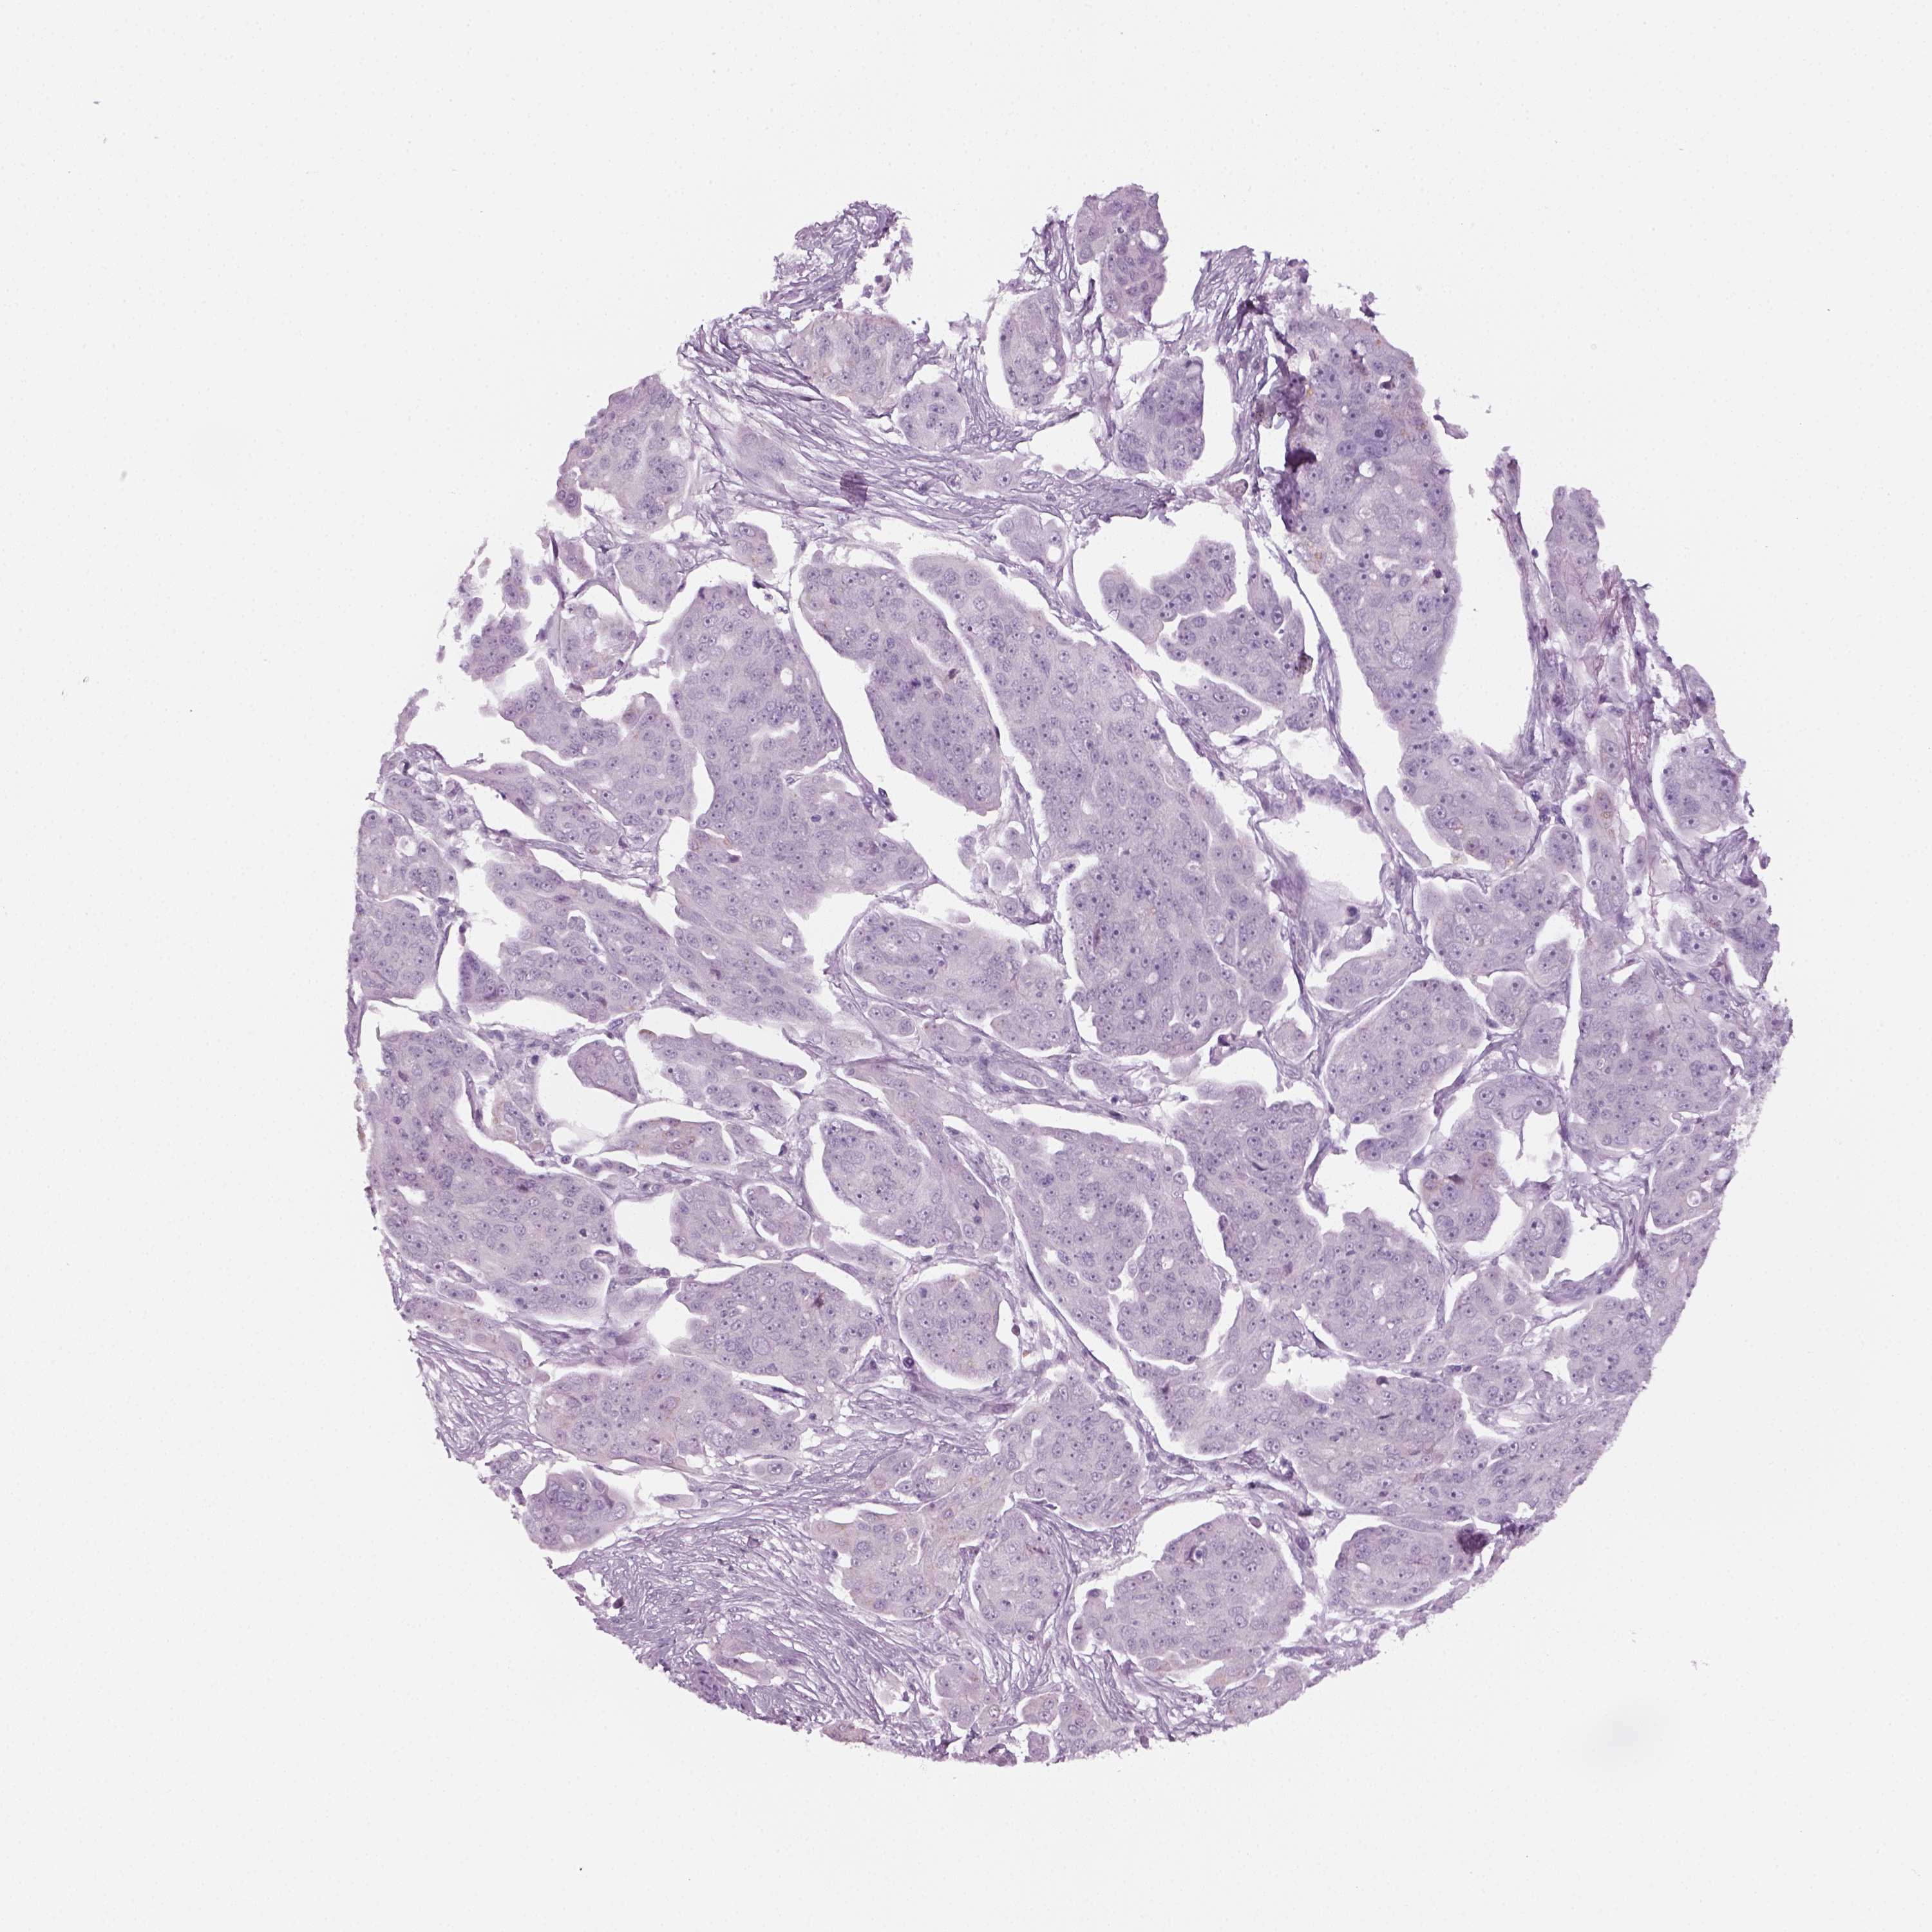

OVARIAN CANCER - Protein expressioni

A mouse-over function shows sample information and annotation data. Click on an image to view it in a full screen mode. Samples can be filtered based on level of antibody staining by selecting one or several of the following categories: high, medium, low and not detected. The assay and annotation is described here.

Note that samples used for immunohistochemistry by the Human Protein Atlas do not correspond to samples in the TCGA dataset.

Antibody stainingi

Antibody staining in the annotated cell types in the current human tissue is reported as not detected, low, medium, or high, based on conventional immunohistochemistry profiling in selected tissues. This score is based on the combination of the staining intensity and fraction of stained cells.

Each image is clickable and will lead to virtual microscopy that enables deeper exploration of all samples and also displays staining intensity scores, fraction scores and subcellular localization as well as patient and tissue information for each sample.

Antibody HPA019367

Antibody HPA076201

Cystadenocarcinoma, serous, NOS